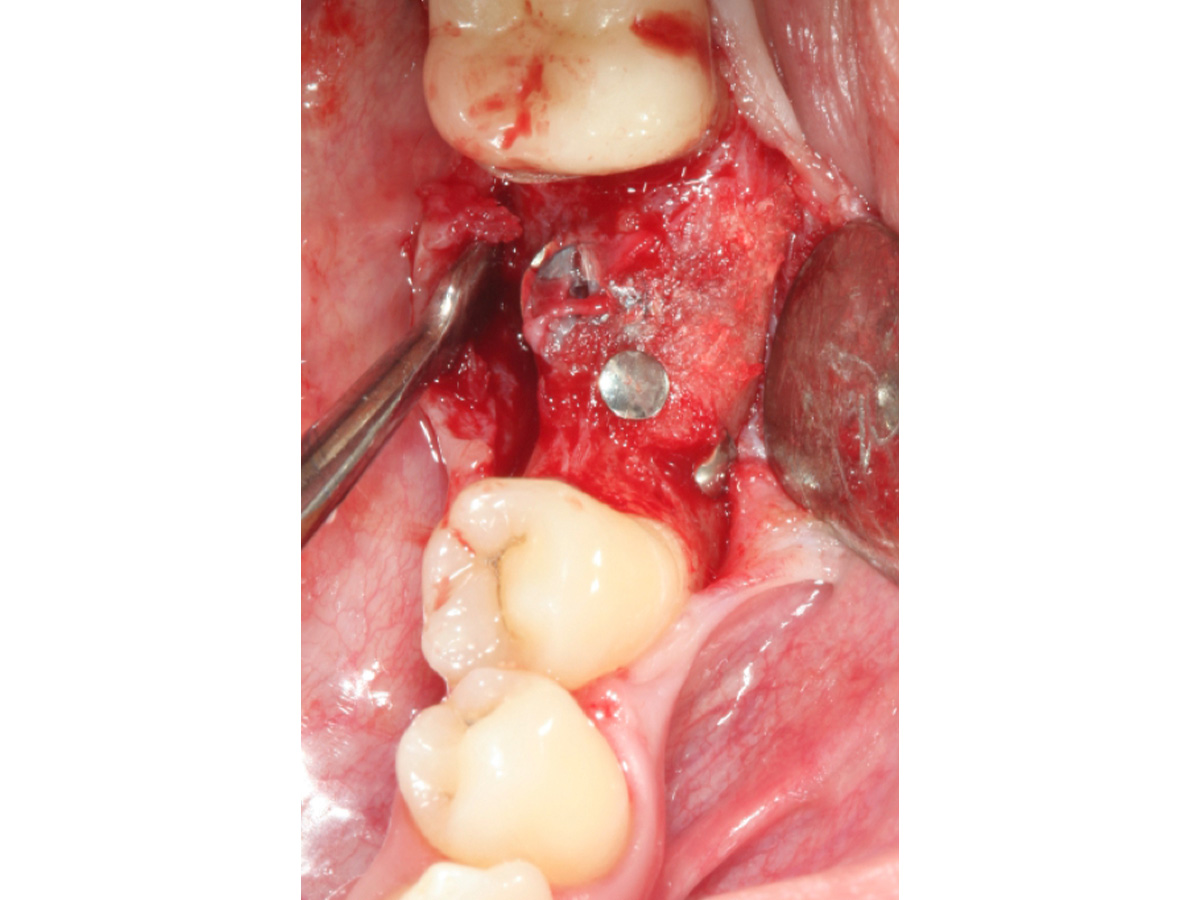

Nach Implantation wurde die zugeschnittene Bone Lamina positioniert und mit Pins fixiert, die Situation danach ist in Abb. 5 zu sehen. Mit dem Instrument wird demonstriert, dass eine „Tasche“ geschaffen wurde, die in Abb. 6 mit mp3® Knochengranulat aufgefüllt wird. Abb. 7 stellt dar, wie die Bone Lamina über den Kopf des Implantates auf den lingualen Anteil des Kieferkammes positioniert wird.

Füllung mit mp3® Knochengranulat.

Abbildung 6